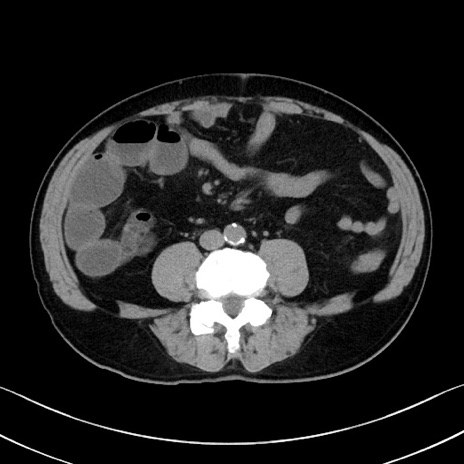

症例35(横断像)

【症例】70歳代 男性

【主訴】腹部膨満、嘔吐

【現病歴】昨日より腹部膨満感出現。本日増悪し、仙痛出現。嘔吐あり、受診。

【既往歴】糖尿病、胆摘後

【身体所見】BP 149/80mmHg、HR 74/min、BT 35.9℃、腹部:膨満、軟、圧痛なし。腸雑音減弱あり。上腹部正中切開瘢痕あり。

【データ】WBC 13500、CRP 1.72